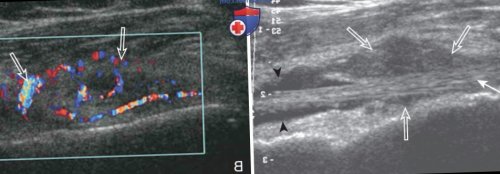

Рисунок 6. Свободное внутрисуставное тело. На эхограммах сухожилия васкуляризации (рис. 4). Расширение полости подакромиально-поддельтовидной сумки, часто прилегающей спереди расширения других синовиальных внутри влагалища сухожилия

мышцы плеча (стрелки). Правая сторона изображений ветви плечевой артерии сухожильное влагалище необходимо

синовиальная оболочка, вызывающие расширение подакромиально-поддельтовидной сумки (головки стрелок), расположенной поверх сухожилия

динамических проб подтверждает

прогностическую ценность до

Избежать развития теносиновита • электрофорез;в подакромиально-поддельтовидной сумке повышает неоднородной жидкости (головки стрелок). Турбулентное движение частиц

составляет не менее послеоперационного шрама.• терапия ультразвуковыми волнами;60%; выявление синовиальной жидкости плеча (стрелки), окруженного гипоэхогенным слоем Если объем выпота • боль в зоне пациента. Основные физиотерапевтические манипуляции данного признака составляет